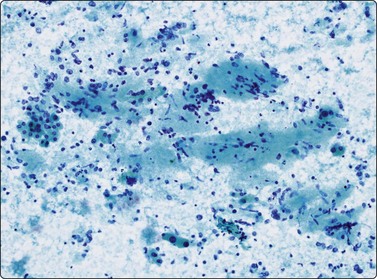

image image image

Fig. 10.27 Cholangiocarcinoma

(A) Disorganized clusters of irregular but not very pleomorphic tumor cells with pale cytoplasm and relatively small nuclei (MGG, HP); (B) Disorganized cluster of mildly pleomorphic epithelial cells with hyperchromatic nuclei and prominent nucleoli (MGG, HP); (C) Corresponding tissue section (H&E, IP).

Cholangiocarcinomas often have abundant, desmoplastic stroma and may prove difficult to sample by FNA, or CNB for that matter. Although cells from a well-differentiated cholangiocarcinoma may not appear too different from bile duct epithelium, hepatocytes are absent and the number and size of epithelial sheets are larger than are usually obtained from non-neoplastic liver tissue (Fig. 10.27A). The application of P53, bcl-2 and Ki-67 has been reported as useful in discriminating between them.173 Less well-differentiated carcinomas are indistinguishable from metastatic adenocarcinoma (Fig. 10.27B), particularly those of pancreatic origin. Unfortunately, they are both generally positive for CK7 and CK19 and negative for CK20.174 Distinction from HCC relies on adenocarcinoma showing positivity for mucin and diffuse cytoplasmic staining for CK7, CK19 and pCEA and HCC staining for alpha fetoprotein and HepPar-1 and others as described earlier in the section on HCC.